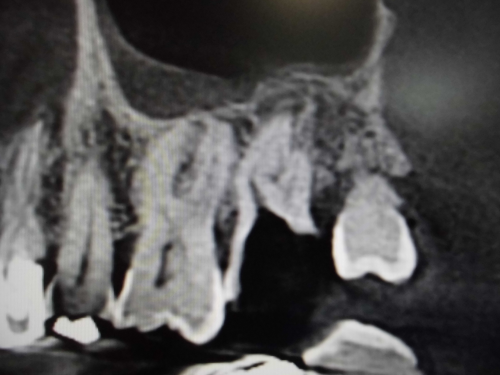

上顎洞との位置関係が確認できます。

CTでは近心の第二根管も確認できます。